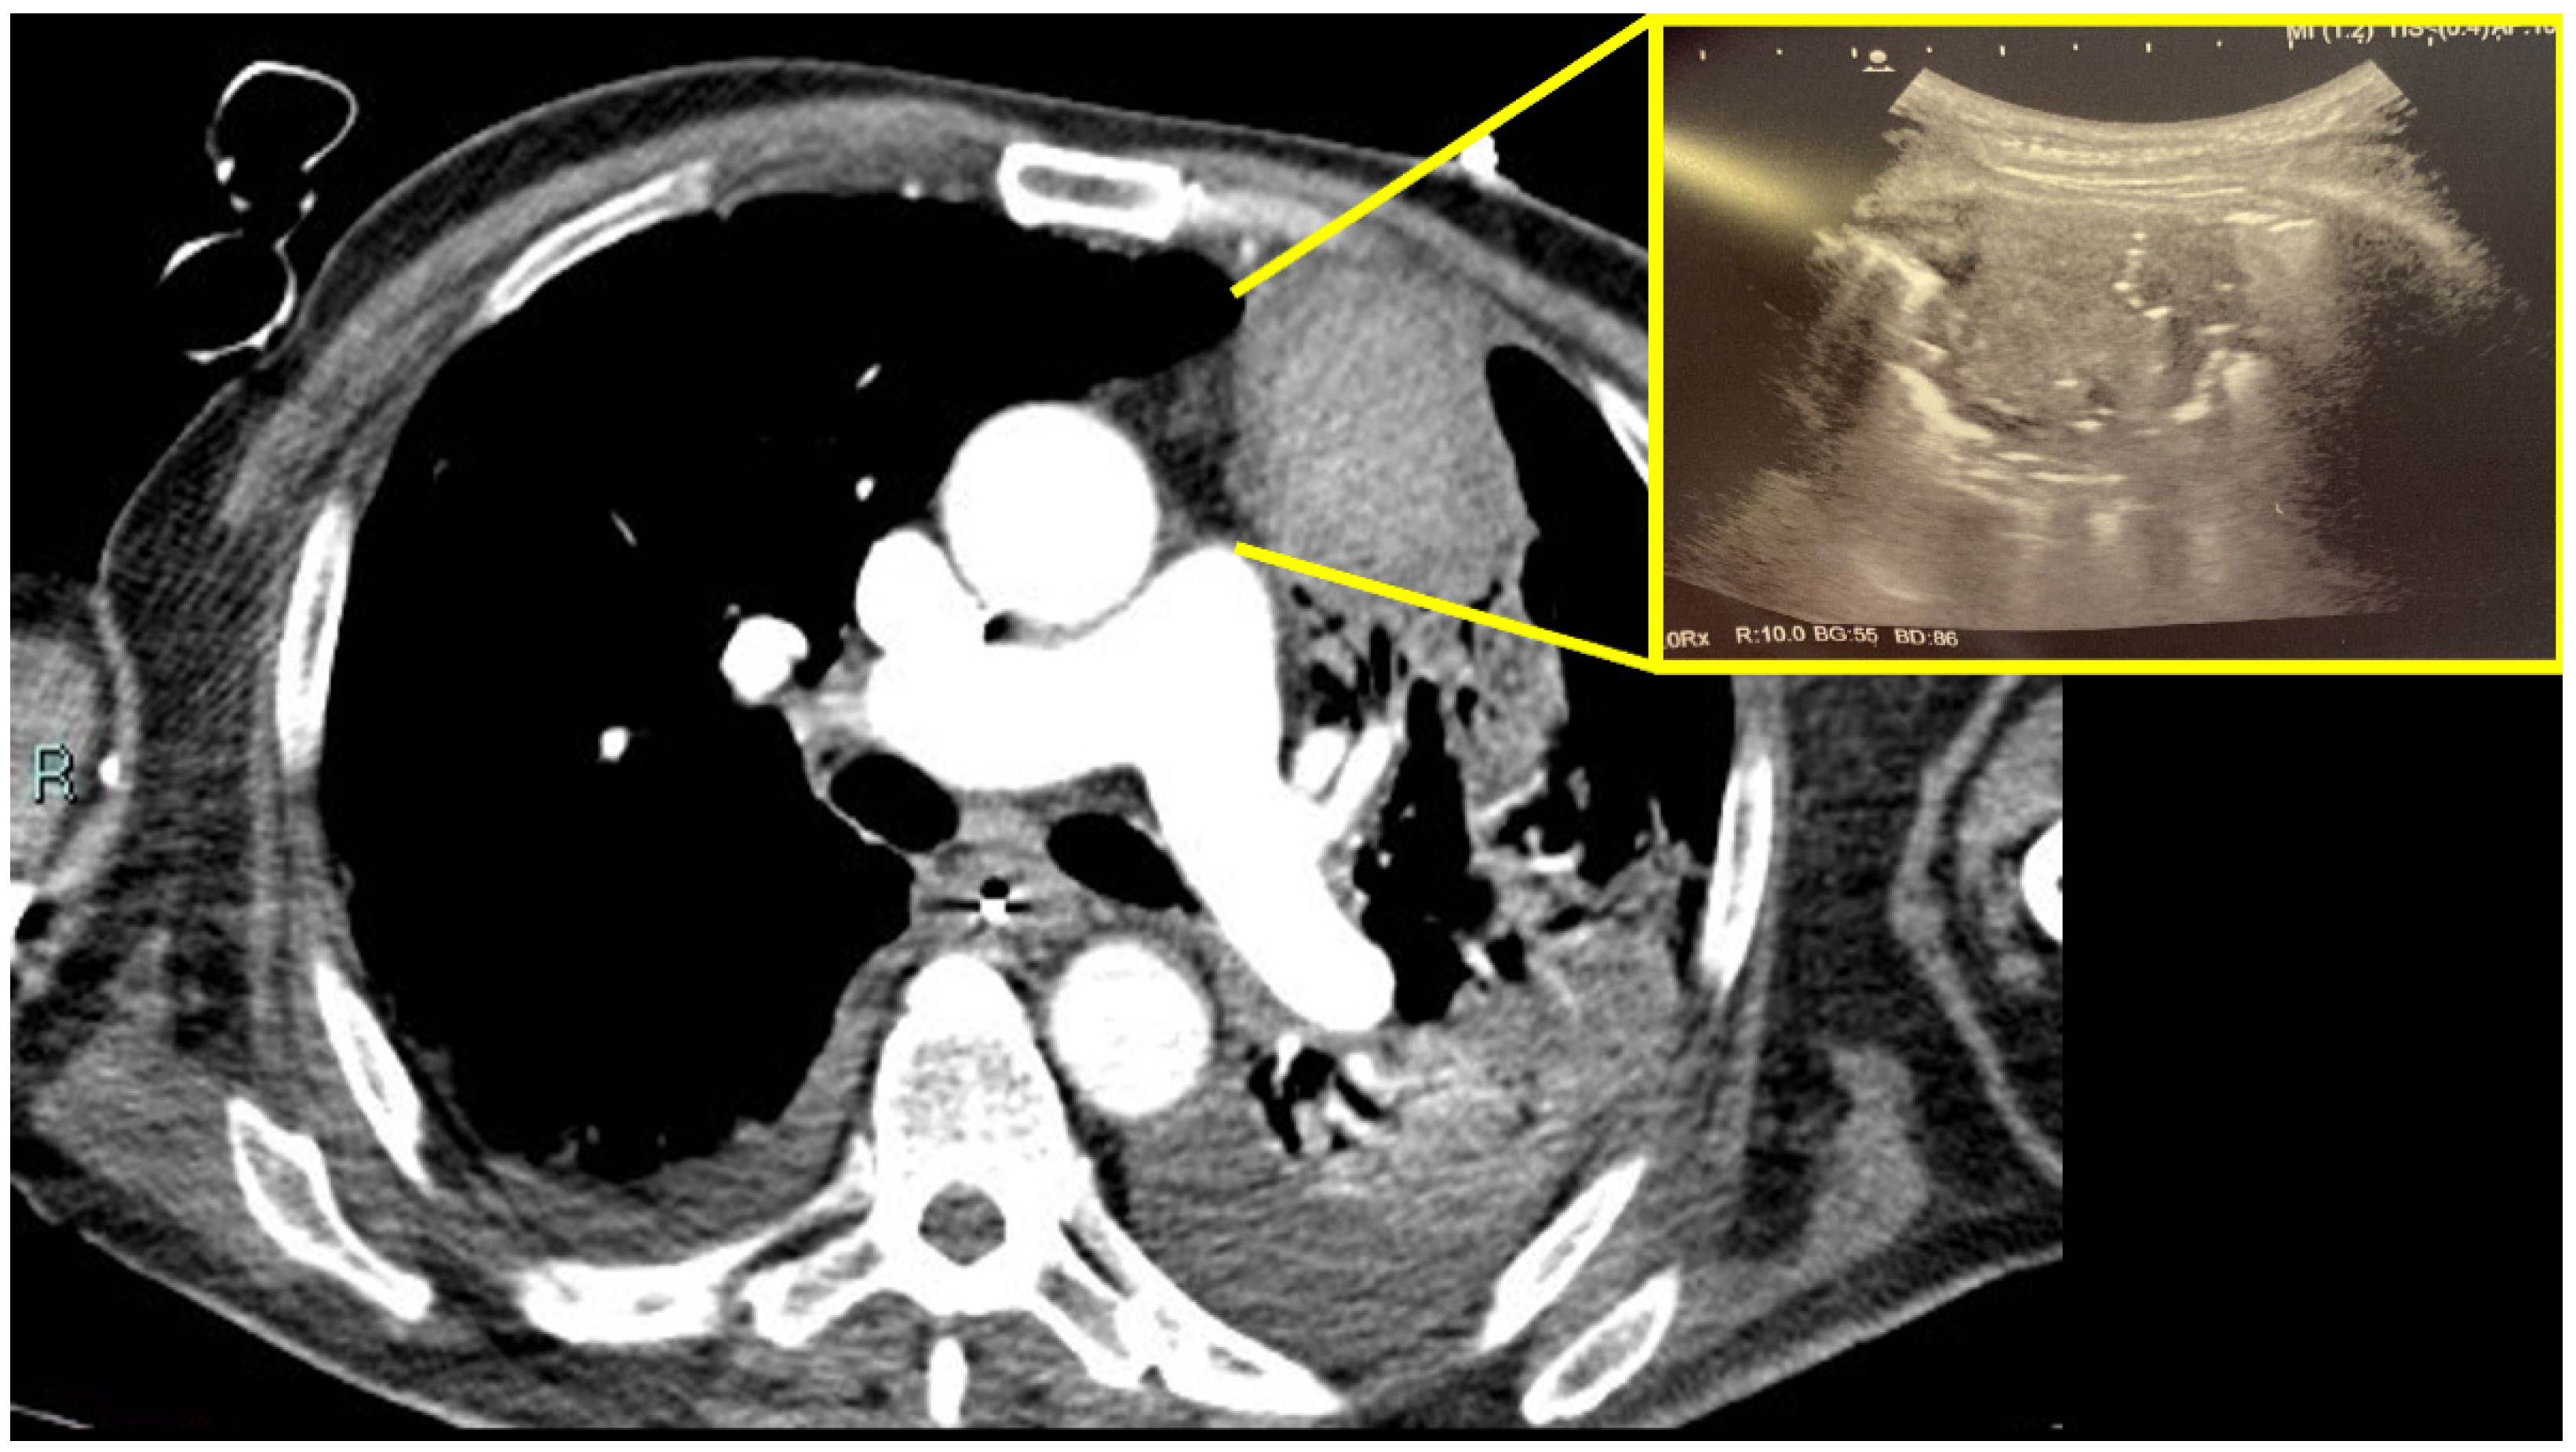

2. Case